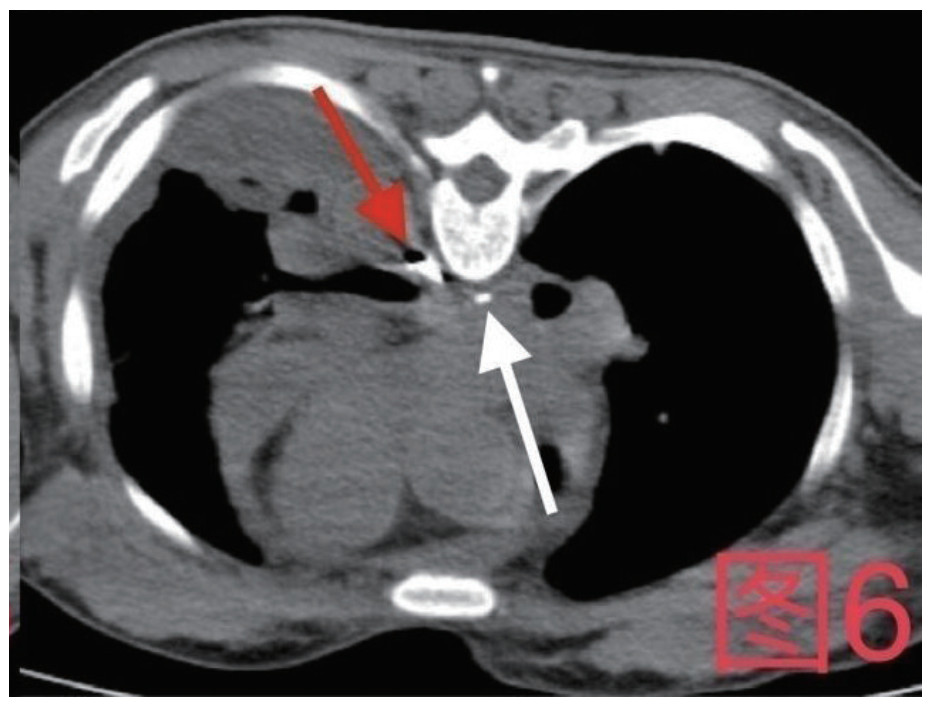

治疗经过:急诊予美罗培南0.5 g,1次/12 h抗感染,补液支持,心包引流等治疗措施,收住感染科后继续抗感染治疗,期间心包积液培养出白假丝酵母菌,加用氟康唑200 mg,1次/d, 口服,心包积液、左侧胸腔积液引流等措施,治疗10 d后复查胸部CT仍有中大量心包积液伴少许积气,纵隔积气;左侧少量胸腔积液,两肺叶间裂少许积液。对照前片(2020.10.26)心包积气及左侧胸前积液有增多,叶间裂积液新发,心包积液略有减少。右肺下叶感染,左肺下叶膨胀不全,较前右肺下叶感染有吸收,左肺下叶膨胀不全新发。考虑不能排除食管纵隔瘘,予口服碘海醇后胸部CT检查(图 3~6):约胸6椎体水平食管纵隔瘘,瘘口为相应水平食管壁右前方可能;胃镜(图 7):食道距门齿25 cm右后壁见一直径约1.0 cm凹陷,内有一小瘘口。胃镜下予钛夹2枚夹闭瘘口(图 8),同时植入空肠营养管。至此患者病情明确诊断食管心包瘘,患者经以上治疗后心包积液、胸腔积液逐渐减少,于11月13日拔除心包及胸腔引流管,因患者签字回当地就诊,予口服莫西沙星、氟康唑带药出院,出院后随访,患者未回当地医院治疗,仅在家中继续空肠营养管饲喂及口服抗菌药物治疗。

图 6 患者俯卧位,白色箭头为纵隔内碘海醇,红色箭头为食管内碘海醇

对食管心包瘘的诊断检查需尽早进行,在急诊工作中我们可以选择口服美蓝观察心包和胸腔引流液染色情况,采取食管造影、口服碘海醇螺旋CT检查或胃镜检查。其中口服碘海醇螺旋CT检查的患者需注意可能因造影剂尚未通过瘘口导致漏诊,如本病例中患者在口服2次碘海醇后检查才出现异常结果,多次检查或改变体位进行食管造影能降低漏诊机会[10-11]。对于高度怀疑的患者进一步的胃镜检查不仅可明确诊断,也可以在诊断后给予食管支架或钛夹等治疗手段以及放置空肠营养管便于早期营养支持等支持措施[12-13]